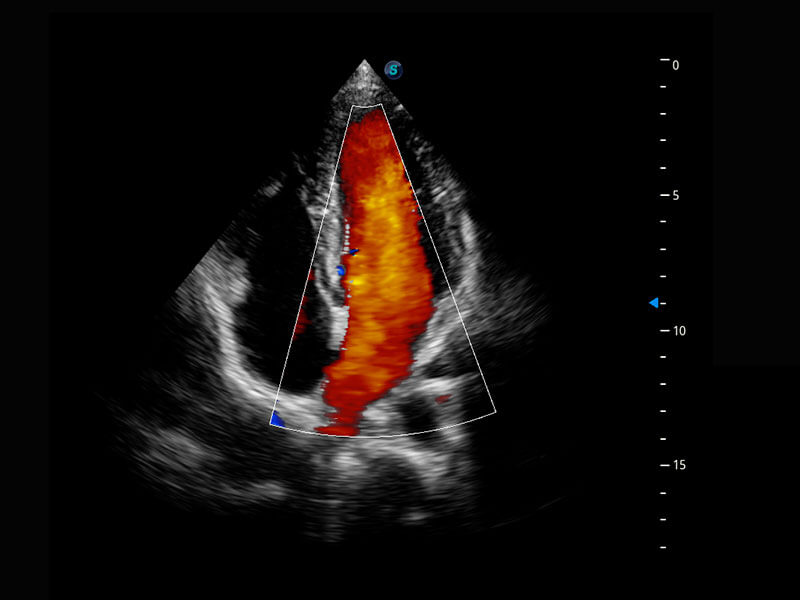

P60搭载宽频带线阵探头、宽景成像、弹性成像技术,为您提供乳腺应用方案。P60支持高频相控阵探头、线阵探头、腹部高频探头、腹部微凸探头等,丰富的探头群搭载敏感的彩色血流成像,适用于新生儿多种脏器检测要求,满足新生儿筛查需求。

新生儿肝血管癌

新生儿脊髓圆锥

新生儿心脏